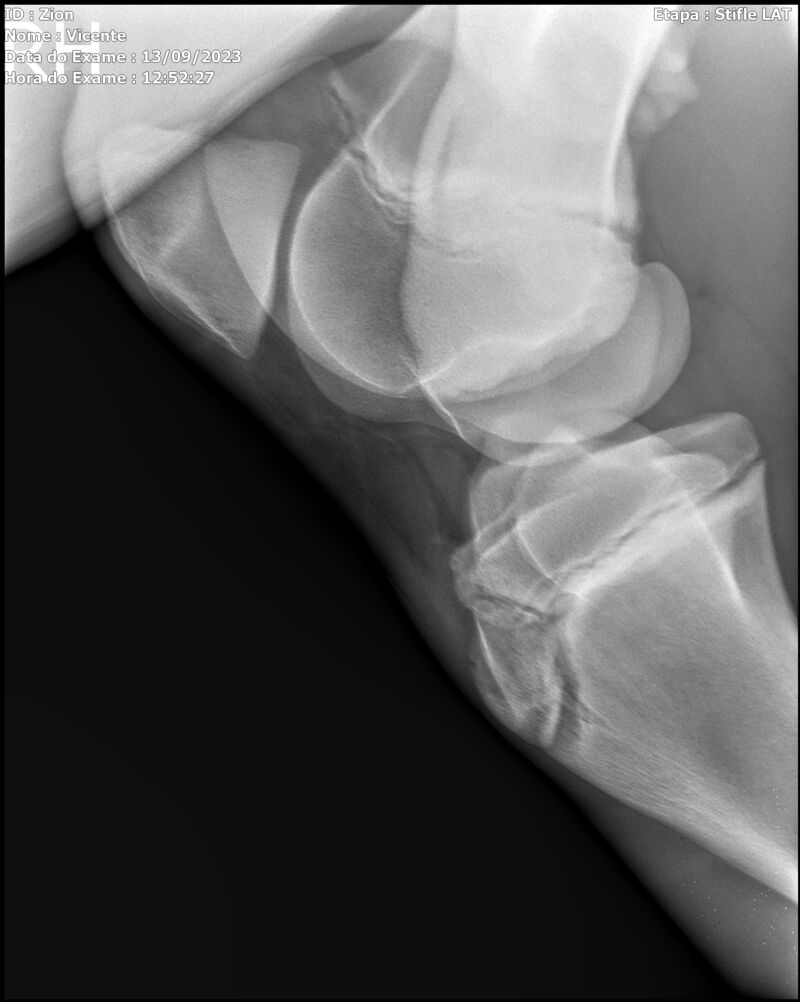

ZION ZC

Raça: BRASILEIRO DE HIPISMO

Sexo: MACHO - POTRO

Nascimento: 17/12/2022

Altura Aproximada: 1,51

Pel.: CASTANHO

Registro: EM AND

Vend.: VICENTE CONTE

Local : PORTO FELIZ/SP